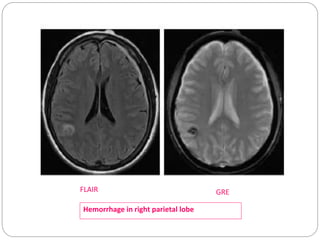

GRE

 In a GRE sequence, an RF pulse is applied that

partly flips the NMV into the transverse plane

(variable flip angle).

 Gradients, as opposed to RF pulses, are used to

dephase (negative gradient) and rephase

(positive gradients) transverse magnetization.

 GRE Sequences contd:

 This feature of GRE sequences is exploited- in

detection of hemorrhage, as the iron in Hb becomes

magnetized locally (produces its own local magnetic

field) and thus dephases the spinning nuclei.

 The technique is particularly helpful for diagnosing

hemorrhagic contusions such as those in the brain .

GREFLAIR

Hemorrhage in right parietal lobe